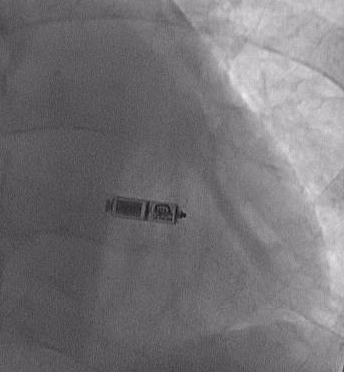

今回のリードレスペースメーカは、ポケットを作成する必要がなく、リードもありません。右室心室中隔心尖部に植込み、VVIRで、電池寿命も約10-14年、MRI対応のデバイスです。